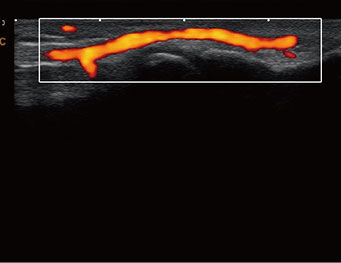

Superficial Vessel 0.2cm depth, CPA Mode

Superficial Vessel 1cm depth, C Mode